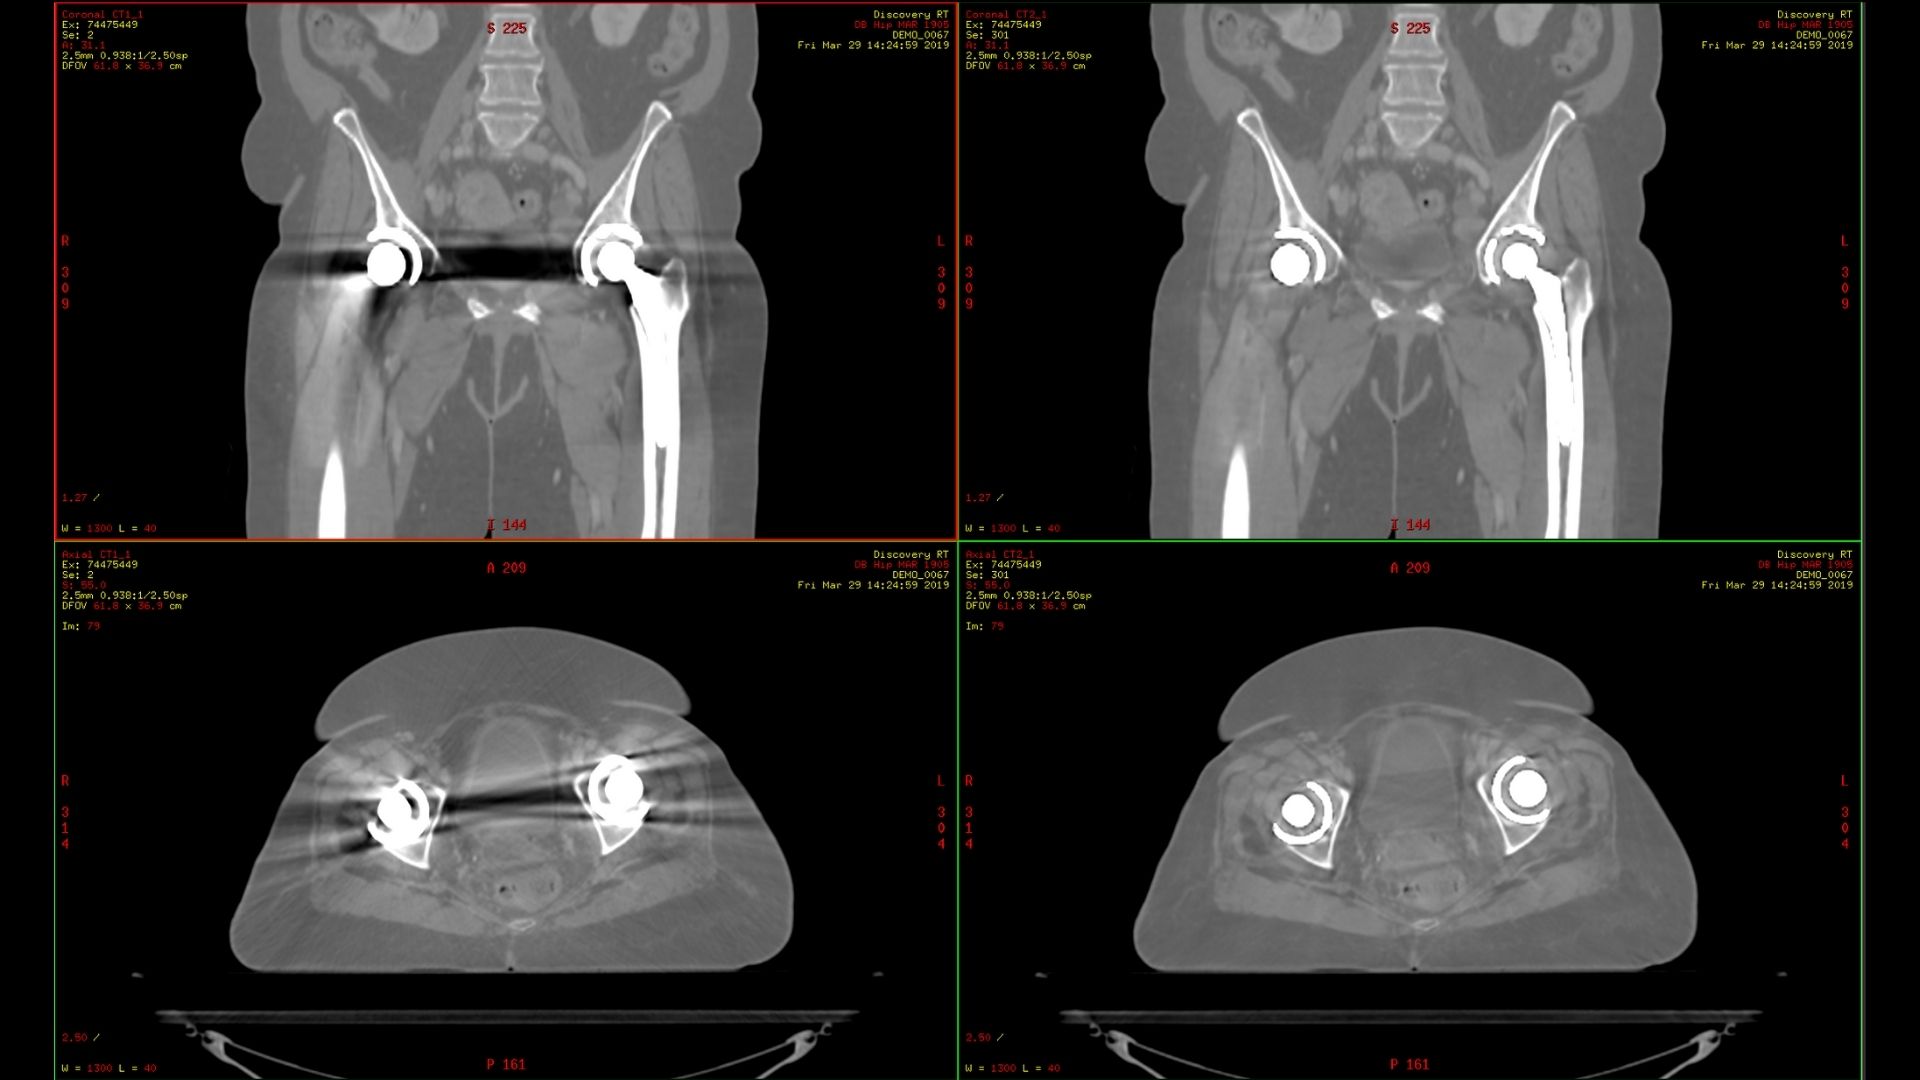

Smart MAR 2.0

Smart MAR 2.0 is designed to reduce artifacts of high-density materials, including orthopedic implants, dental fillings, and other metal in the body. Our metal artifact correction technology is based on raw data, enabling you to reduce artifacts caused by both photon starvation and beam hardening, revealing the anatomy that was concealed all the way out to the edge of the bore.